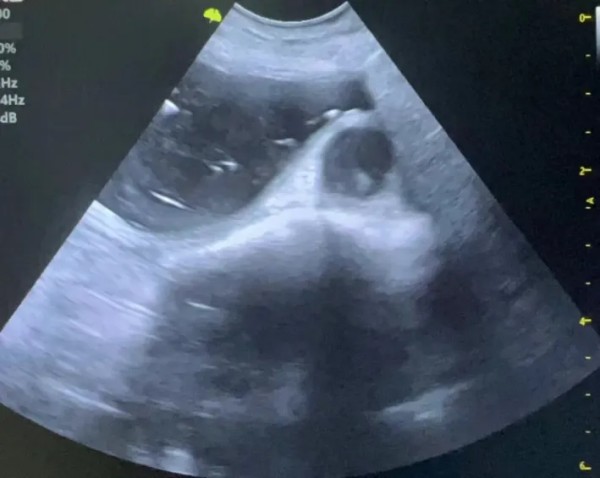

04【超声下表现】 (1)正常子宫影像 (2)子宫残端积液影像 (图片来源:Mattoon, J. S., Sellon, R. K., & Berry, C. R. (2020). Small animal diagnostic ultrasound (4th ed.). Elsevier Saunders.)

05【诊断】 (1)病史:有绝育手术史,之后出现上述症状。 (2)体格检查:腹部触诊可能摸到腹内的团块。 (3)影像学检查: ① 超声:这是首选的、最具诊断价值的方法。可以清晰地看到膀胱附近有一个充满液体的囊状结构(子宫残端),并能评估其大小、壁的厚度和内容物性质。 ② X光:如果积液量很大,可能在X光下看到一个软组织密度的团块影,但不如B超直观。 (4)血液检查: ① 血常规:如果发生感染/蓄脓,白细胞会显著升高。 ② 激素水平检测:检测血清中的孕激素或抗穆勒氏管激素(AMH)水平,可以确认是否存在有功能的卵巢组织残留(即OSS)。这是诊断OSS的金标准。 ③ 阴道细胞学检查:如果有阴道分泌物,可以检查分泌物中的细胞类型,判断是否存在感染和激素影响。